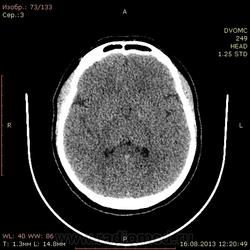

21 год. На момент исследования жалоб нет. DICOM здесь http://files.mail.ru/062AC0004DF8471CAC95B38693A0153C

Что за уплотнение в базальных ганглиях слева? Мелкое начинающееся обызвествление? В таком возрасте?

Нет ли сужения борозд? Прошу оценить их глубину т.к. у самого еще не сформировалось чисто визуальная мера(только третьи мозги в моей практике

Обызвествление базальных ядер в таком возрасте-норма.

Третьи мозги, говорите. Не переживайте. КТ достаточно грубый метод, при травме в мозгу что-то видно только у больных, доставленных в кабинет на каталке. Такие борозды и должны быть у непъющего молодого человека. И обызвествление базальных ядер, тоже клинического значения не имеет (по крайней мере, не встречал). Правда, есть еще синдром Фарра, но то другой случай, там, в первую очередь идет клиника. Какой-то странный у вас протокол, наверное на SDH (субдуральную гематому). Желательно добавить в протокол восстановление из сырых данных с другим фильтром и другой толщиной (например, 5мм).

У вас же спираль идет? Так реконструируйте толстые срезы, по 4-5 мм. Ведь на тонких срезах зернистость увеличивается. И еще нужно добавить немного силы тока, это тоже улучшит изображение.